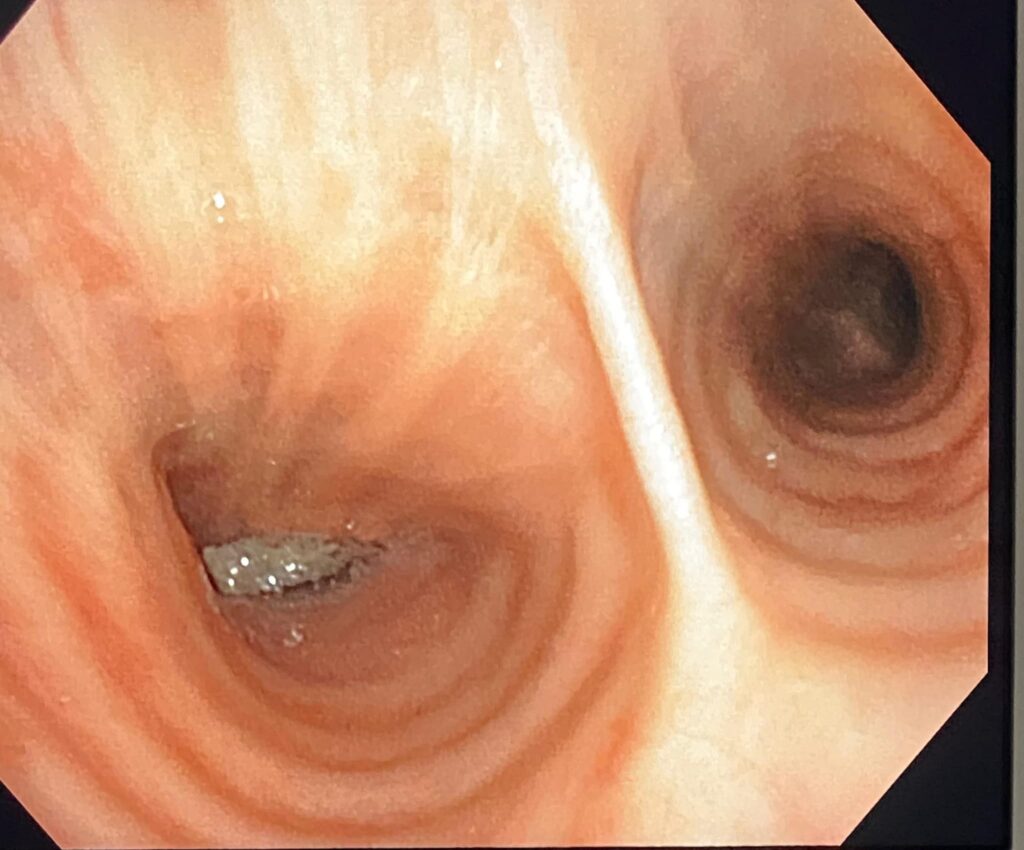

Echipa medicală a Laboratorului de Explorări Funcționale și Endoscopie Bronșică, din cadrul Spitalului de Pneumoftiziologie Sibiu, a reușit să extragă din plămânul unui pacient un os de dimensiuni mari (11 mm x 10 mm). Este vorba despre un sibian în vârstă de 63 de ani, intervenția medicală fiind efectuată de către domnul doctor Ioan Drăghilă, medic pneumolog, cu ajutorul fiber bronhoscopului, aparat aflat în dotarea laboratorului.

„Corpii endobronșici străini la adulți sunt o raritate. De obicei, pacientul uită momentul aspirării corpului străin și pot genera o simptomatologie respiratorie trenantă. La pacientul nostru, retrospectiv, am aflat că momentul inhalării corpului străin a fost în luna februarie, deci în urmă cu circa 4 luni, timp în care pacientul a continuat să prezinte tuse și infecții respiratorii repetate. La examenul CT , pentru că nu exista diagnostic, s-a relevat prezența unui corp străin cu aspect de os, în plămân, acest corp străin fiind extras cu succes de către echipa de bronhologie a Spitalului de Pneumoftiziologie Sibiu, după o pregătire prealabilă corespunzătoare a pacientului. Sperăm că evoluția post intervenție va fi favorabilă și în acest fel episoadele pneumonice repetate pe care pacientul le-a prezentat, să nu se mai repete” – a declarat dr. Ioan Drăghilă, medic pneumolog, șeful Secției Pneumologie II din cadrul Spitalului de Pneumoftiziologie Sibiu.

Imaginile extracției: